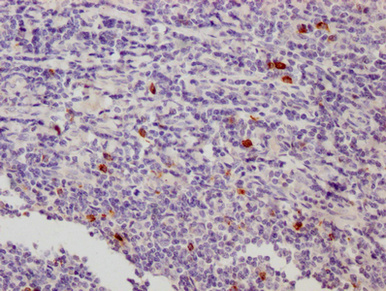

IHC image of CSB-MA012719A0m diluted at 1:500 and staining in paraffin-embedded human tonsil tissue performed on a Leica BondTM system. After dewaxing and hydration, antigen retrieval was mediated by high pressure in a citrate buffer (pH 6.0). Section was blocked with 10% normal goat serum 30min at 37°C Then primary antibody (1% BSA) was incubated at 4°C overnight. The primary is detected by a Goat anti-Mouse IgG labeled by HRP and visualized using 0.05% DAB.

IHC image of CSB-MA012719A0m diluted at 1:500 and staining in paraffin-embedded human appendix tissue performed on a Leica BondTM system. After dewaxing and hydration, antigen retrieval was mediated by high pressure in a citrate buffer (pH 6.0). Section was blocked with 10% normal goat serum 30min at 37°C Then primary antibody (1% BSA) was incubated at 4°C overnight. The primary is detected by a Goat anti-Mouse IgG labeled by HRP and visualized using 0.05% DAB.